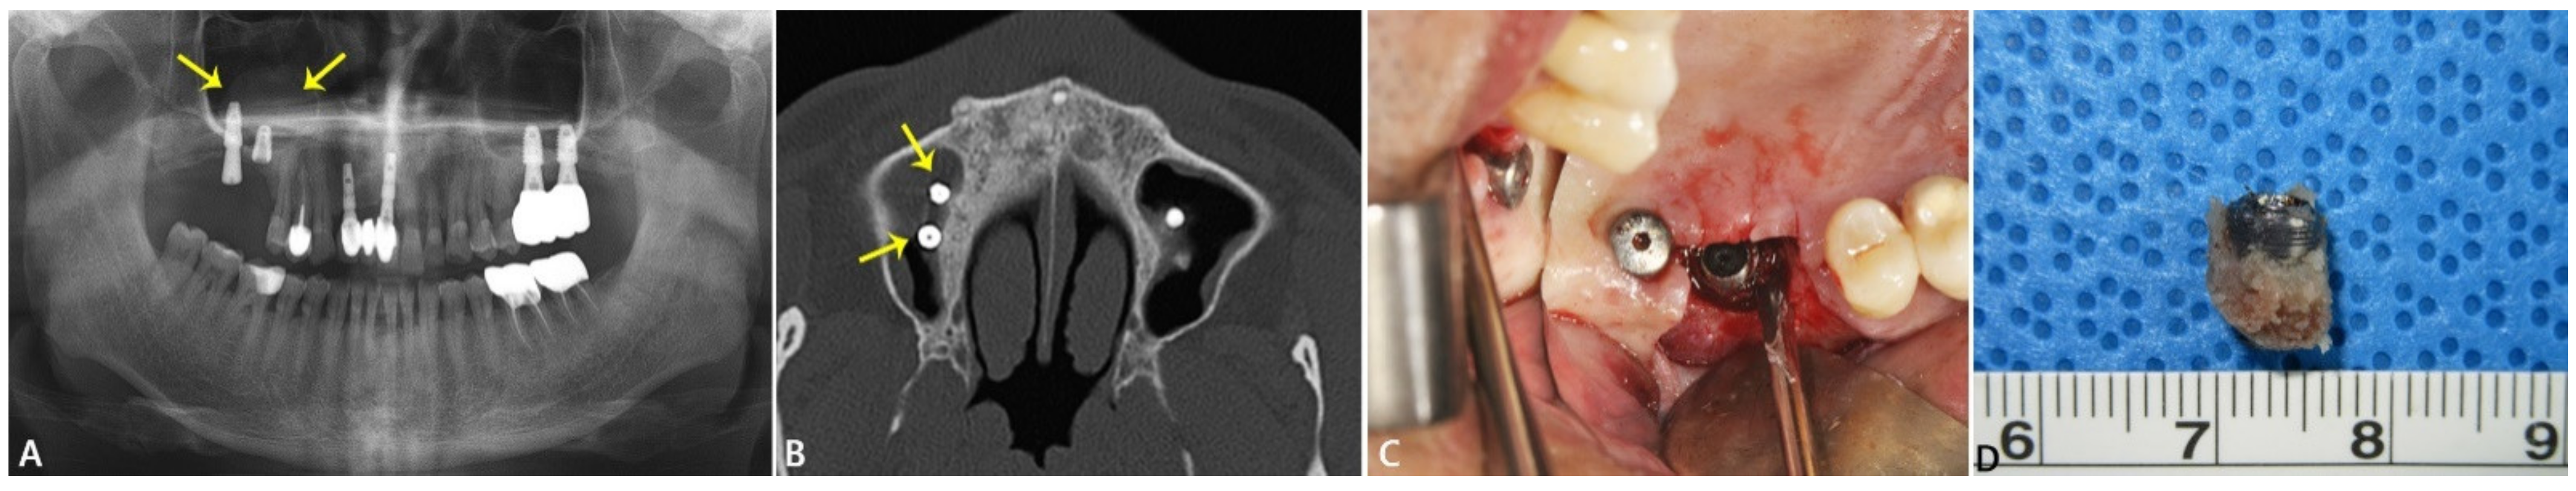

2.1.1. Case 1: Fractured and Damaged Implant-Related Sinusitis Case

| No. 1 | Maxillary sinusitis, retention pseudocyst | #16i | Implant surface at the first thread of the fixture (0101-T) | Ti: 82.98% O: 10.93% | C: 3.58% F: 1.07% | Au: 0.59% Na: 0.37 %Ca: 0.32% Si: 0.16% | The SEM image showed the typical morphology of the sandblasted and acid-etched surface with signs of oxidation. |

| Ti level in the normal range Presence of organic components/particles Contaminating significant level of C, F Traces of Au, Na, Si, Ca | |||||||

| Bone tissue in the upper region (0102-U) | Ca: 35.61% O: 24.86% C: 19.97% | Zr: 9.19% P: 8.7% | Ti: 0.64% Na: 0.58% Si: 0.45% | Bone tissue showed irregular structure. | |||

| Ca/P ratio: 4.1 → turn over bone High level of O and C → large portion of organic contents Homogenous distribution of Ti and Zr ions in the bone tissue. | |||||||

| Bone tissue in the apical region (0103-A) | O: 31.18% Ca: 29.26% C: 22.02% P: 11.2% | Na: 2.17% Si: 1.87% Ti: 1.22% | Au: 0.56% Al: 0.32% Mg:0.19% | SEM image showed the bone surface with debris and particles. | |||

| Ca/P ratio: 2.6 Ti particle was detected on the EDS elemental distribution map. Minor levels of Na and Si Trace metals included Au, Al, Mg | |||||||